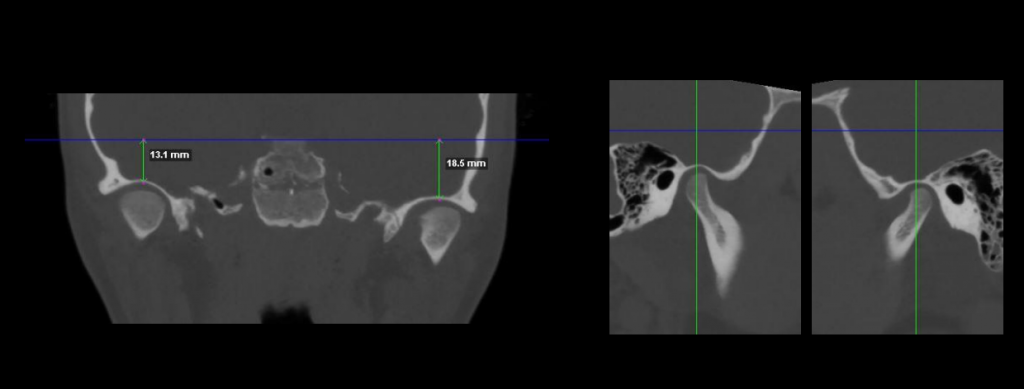

Cada paciente y cada tratamiento es único. El profundo conocimiento de la anatomía y de nuestros pacientes junto con la tecnología más avanzada nos permite realizar diagnósticos certeros. Localizando el origen del problema muchas veces incluso antes de que se produzca evitando así su aparición.